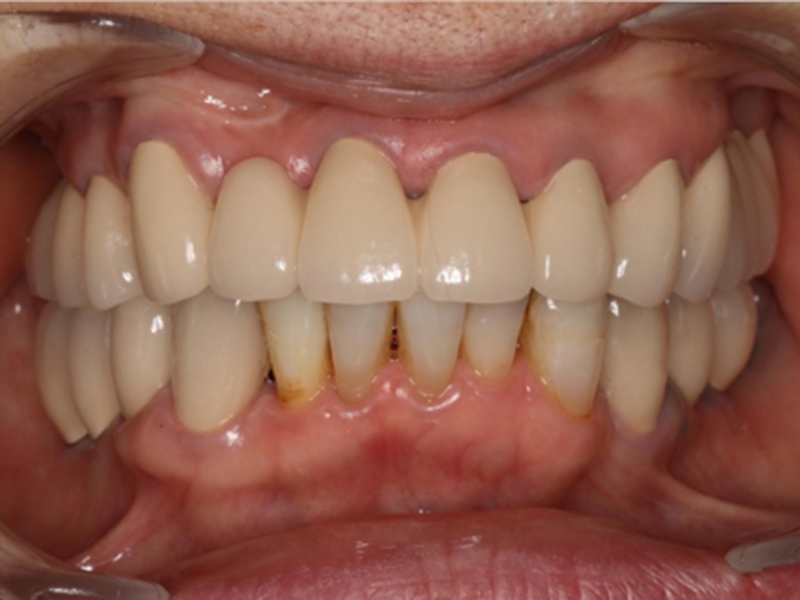

治療終了時口腔内写真